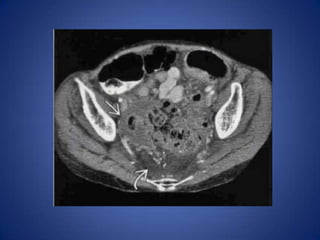

Diverticulitis • Most commoncause in middle-aged and elderly – Can affect patients as young as 25 • Usually long ( 10- 1 5 cm) segment of wall thickening, luminal narrowing, pericolonic infiltration • Extraluminal collections of gas or fluid help confirm diagnosis

Colon Carcinoma • Usuallyshort segment without much pericolonic infiltration • Regional lymphadenopathy has strong association with carcinoma, rarely seen in diverticulitis • Acute symptoms may be due to colonic obstruction ± colitis proximal to the obstructing mass